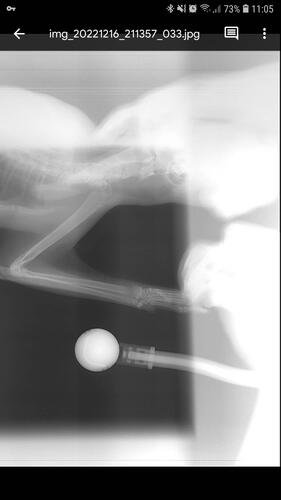

Depois de algumas consultas e até mesmo um diagnóstico errado, enfim descobriram que eu estava com as patinhas fraturadas, e pela forma como estavam a explicação era apenas uma: fui mais um alvo da maldade humana.

Eu preciso operar as patas o quanto antes, pois venho tendo perda óssea e mal consigo usar minha caixa de areia. Vivo apenas deitada e é minha mãe quem me alimenta e me da água na boca, além de levar na caixina, pois como podem ver nas fotos, minhas patas estão tortinhas e não consigo mais o mínimo de apoio.